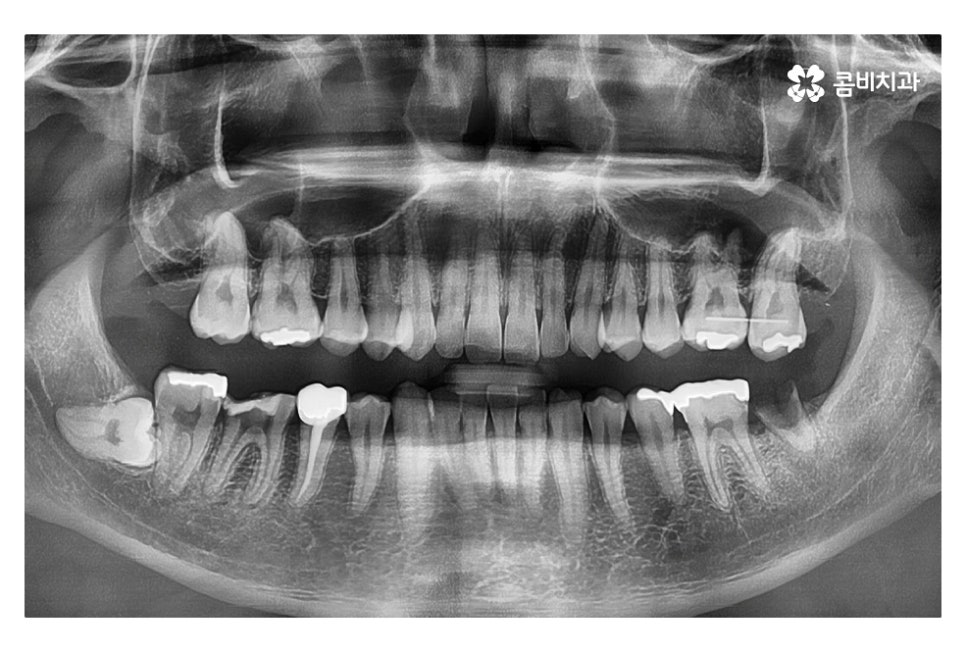

같은 환자분의 사진인데 좌측 치아의 경우 신경치료 후 크라운으로

마무리를 했지만 우측 어금니의 경우 치아의 대부분이

손상이 되어 결국 발치 후 임플란트를 하게 된 사례라고 할 수 있는데요.